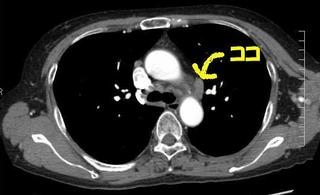

CTで見ると…

3Dだと、こうなります。

気管狭窄ですね。こういう所見もレントゲンで捉えることができるのです。